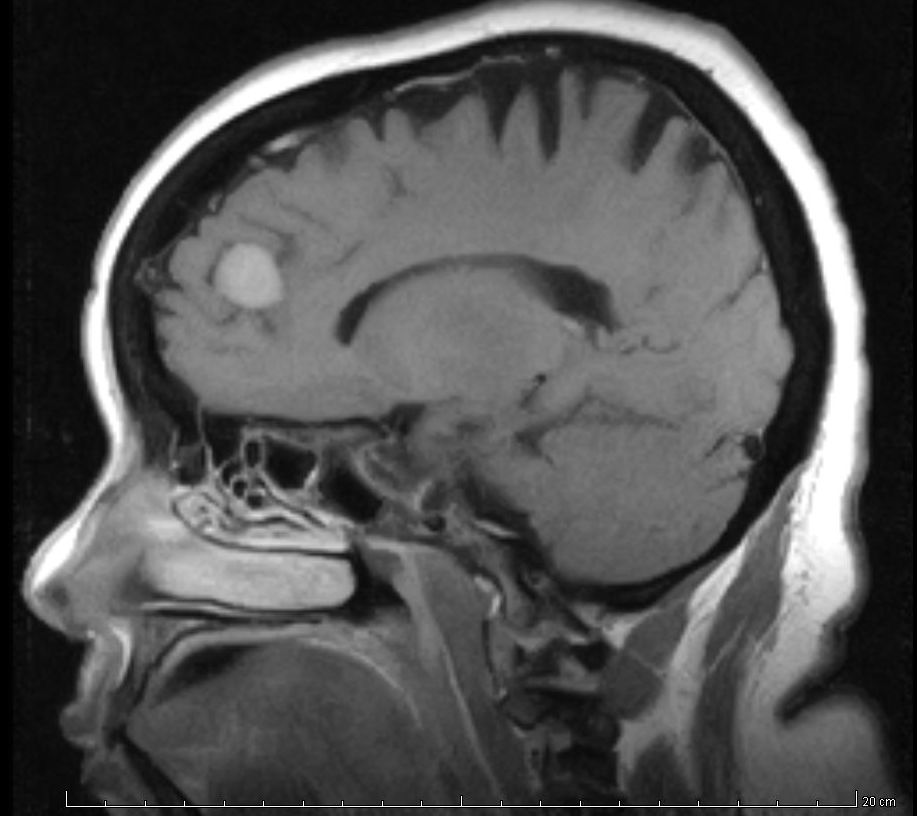

Hallazgos incidentales en resonancia magnética

Se revisa la frecuencia y la gravedad de los hallazgos inesperados en resonancias de cerebro, tórax y abdomen. British Medical Journal, 22 de noviembre de 2018